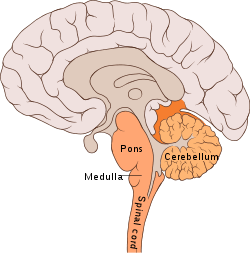

Bulbar polio

Making up about 2% of cases of paralytic polio, bulbar polio occurs when poliovirus invades and destroys nerves within the bulbar region of the brain stem.[1] The bulbar region is a white matter pathway that connects the cerebral cortex to the brain stem. The destruction of these nerves weakens the muscles supplied by the cranial nerves, producing symptoms of encephalitis, and causes difficulty breathing, speaking and swallowing.[14] Critical nerves affected are the glossopharyngeal nerve (which partially controls swallowing and functions in the throat, tongue movement, and taste), the vagus nerve (which sends signals to the heart, intestines, and lungs), and the accessory nerve (which controls upper neck movement). Due to the effect on swallowing, secretions of mucus may build up in the airway, causing suffocation.[37] Other signs and symptoms include facial weakness (caused by destruction of the trigeminal nerve and facial nerve, which innervate the cheeks, tear ducts, gums, and muscles of the face, among other structures), double vision, difficulty in chewing, and abnormal respiratory rate, depth, and rhythm (which may lead to respiratory arrest). Pulmonary edema and shock are also possible and may be fatal.[43]

Bulbospinal polio

Approximately 19% of all paralytic polio cases have both bulbar and spinal symptoms; this subtype is called respiratory or bulbospinal polio.[1] Here, the virus affects the upper part of the cervical spinal cord (cervical vertebrae C3 through C5), and paralysis of the diaphragm occurs. The critical nerves affected are the phrenic nerve (which drives the diaphragm to inflate the lungs) and those that drive the muscles needed for swallowing. By destroying these nerves, this form of polio affects breathing, making it difficult or impossible for the patient to breathe without the support of a ventilator. It can lead to paralysis of the arms and legs and may also affect swallowing and heart functions.[44]